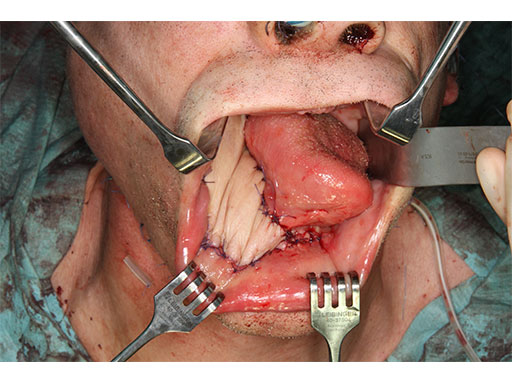

A 58-year-old male patient had oral cancer (T4n0m0) infiltrating the alveolar process and the anterior border of the ascending ramus (Fig 2). The treatment plan involved resection, bilateral neck dissection (levels I to III), and primary mandibular reconstruction with a right osteomyofasciocutaneous fibula flap.

The bony surface of the mandible is covered with a tumor infiltrated soft envelope. The SLS resection guides are screw-fixated in place.

Prior to the resection with a reciprocating saw, the plate screw holes are predrilled using a metal drill guide, which is introduced into the cylinders of the SLS resection guides.